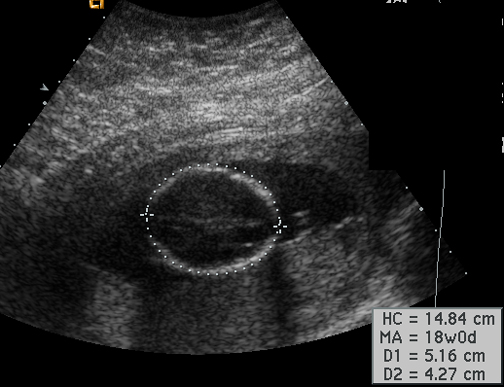

Fetal head circumference Answer